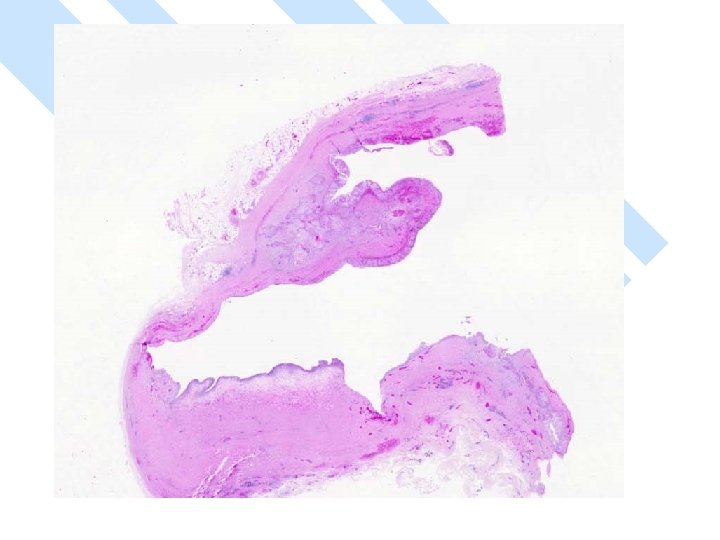

Gross: -A ruptured cyst with attached breast tissue measuring 8. 5 x 6 x 2. 8 cm - area of hemorrhage in cyst wall

Gross n Size: – vary 1 -10 cm – > 50% > 5 cm – Larger than other types of breast cancer. n Cystic > 50%

Micro n Exclude metastasis – Most common sites: lung, uterine cervix, urinary bladder. – Cystic degeneration NOT seen in metastatic carcinoma

Micro The strongest evidence of a primary SCC of breast is presence of in-situ squamous carcinoma in duct or cyst lining.